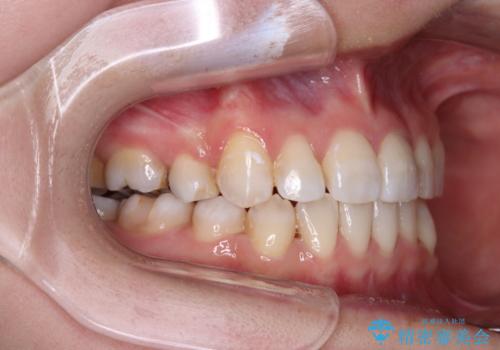

八重歯のためずれていた上下の正中をほぼ一致する位置に整えることができました。

重なって汚れの溜まりやすかった部分も改善され、大変満足していただけました。